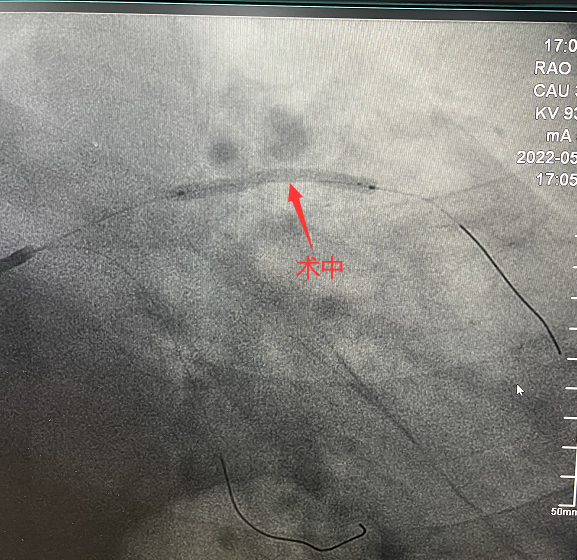

可吸收支架植入手術中

手術造影圖